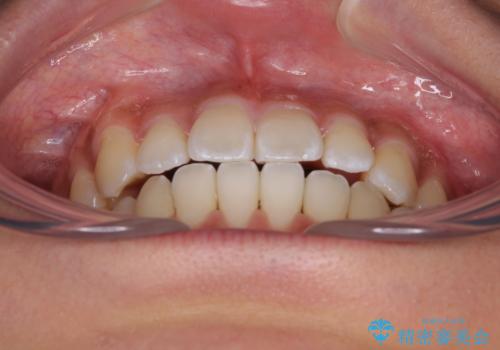

急速拡大装置で上顎骨を十分に拡大できたことで、非抜歯で八重歯を歯列に納めることができました。

患者様はもちろん、我々もここまで綺麗に仕上げられるとは想像もできず、お互いに大変満足な治療となりました。